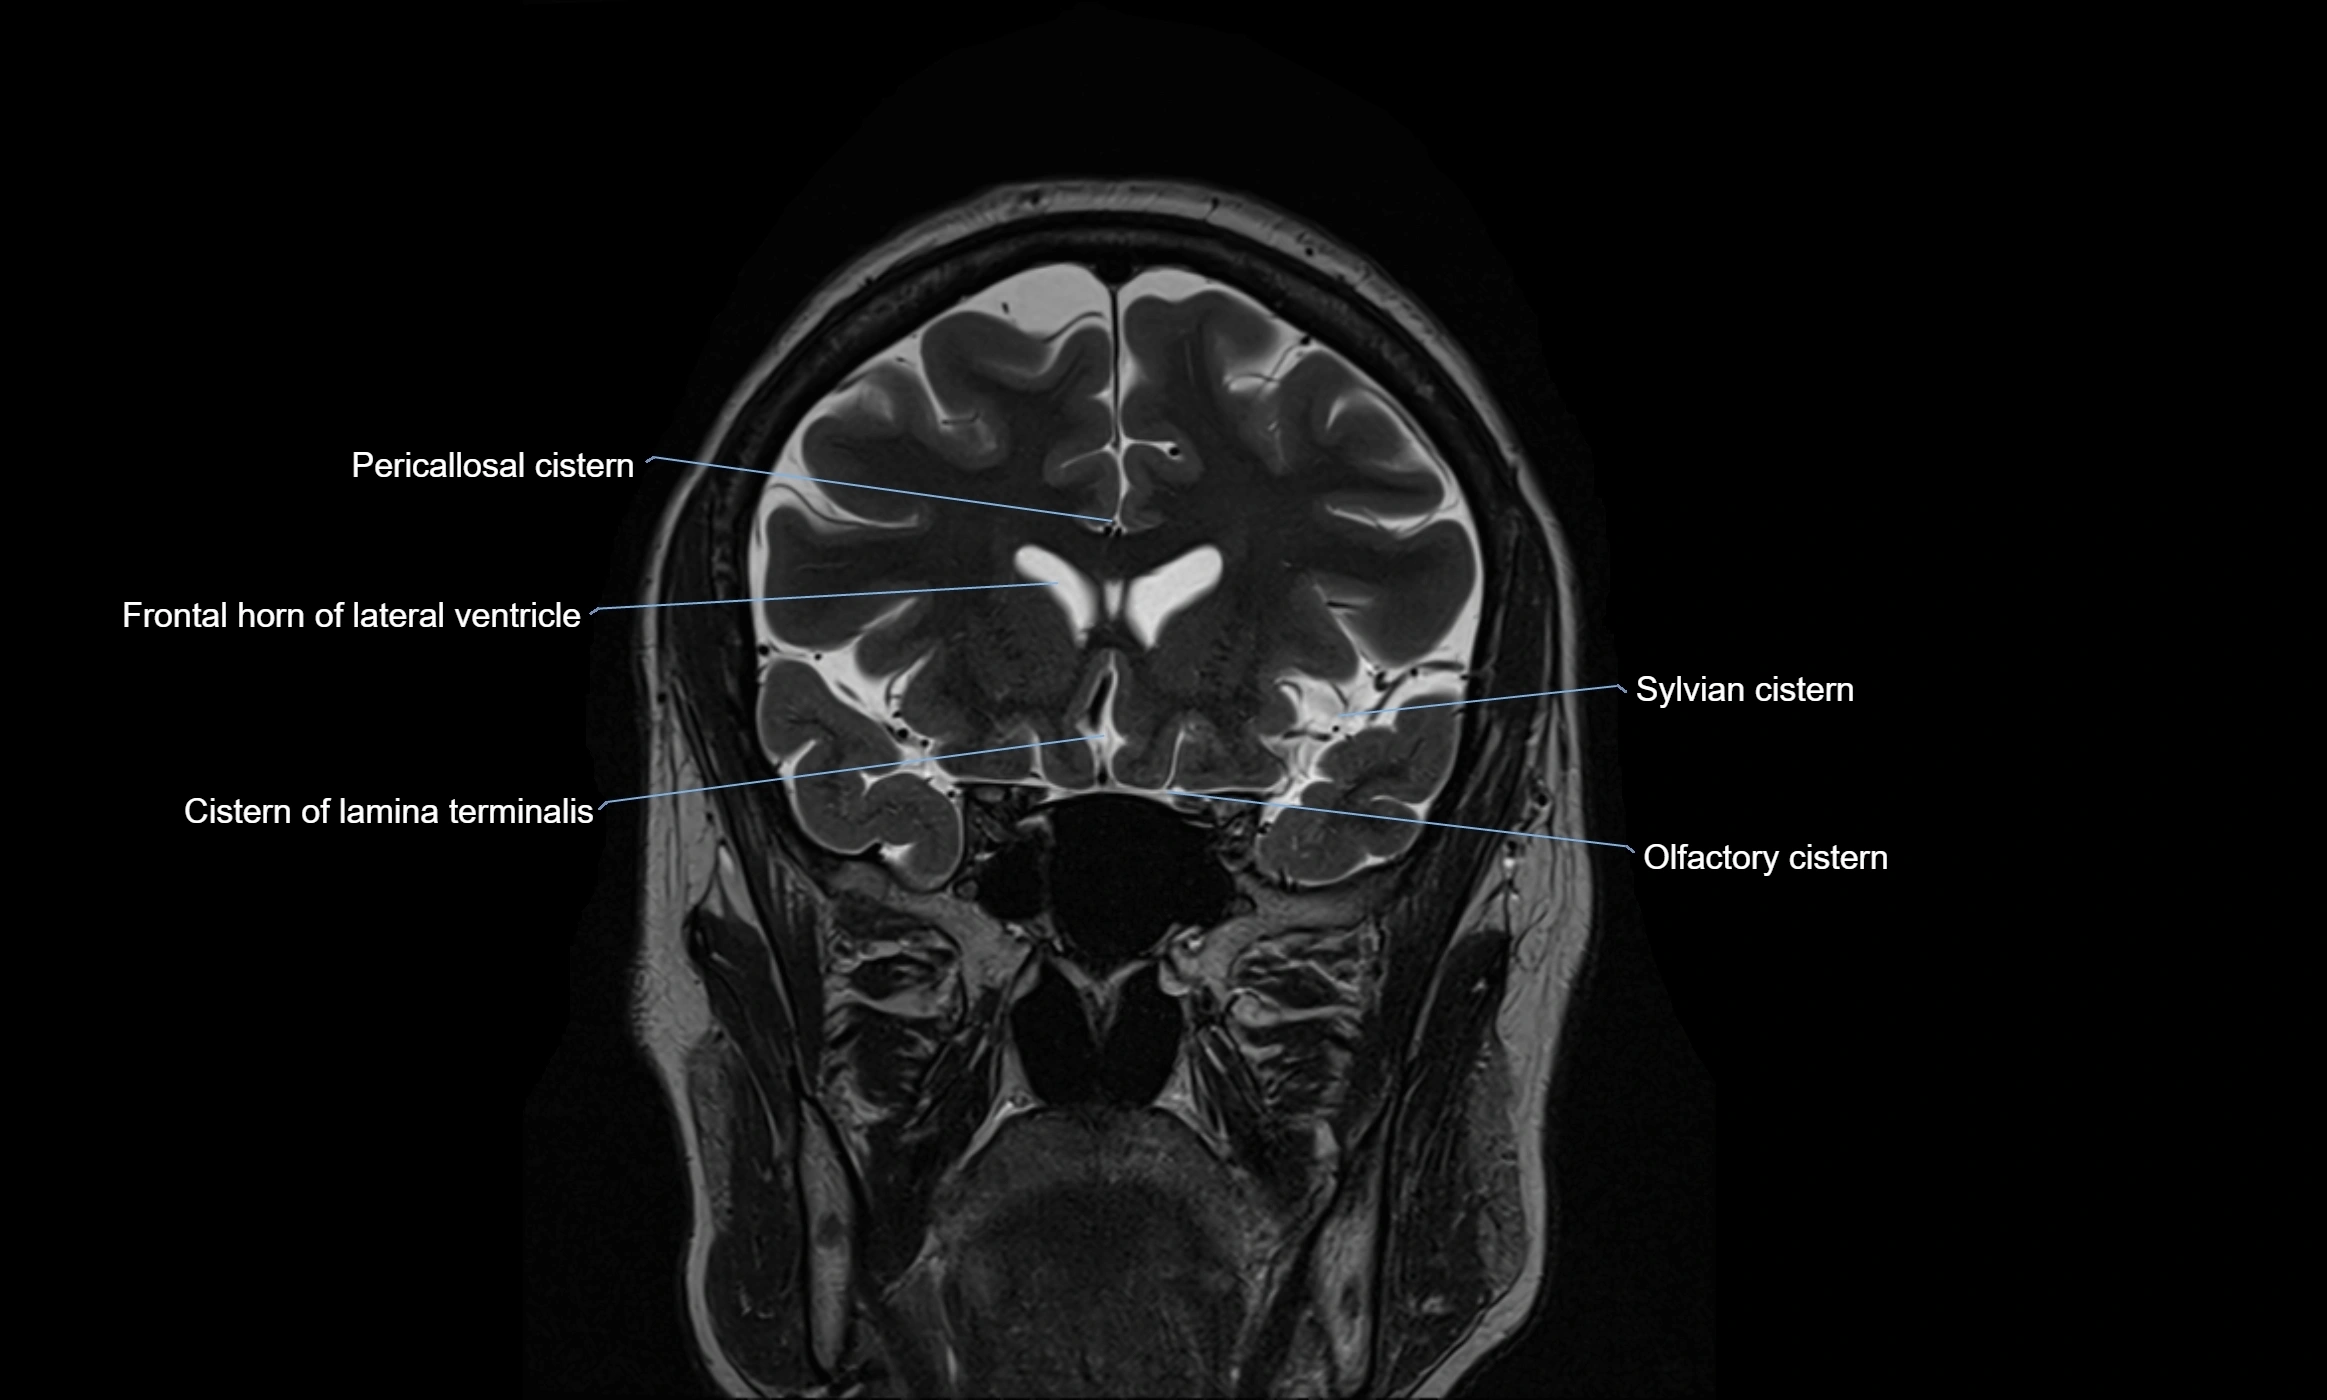

CT image

image